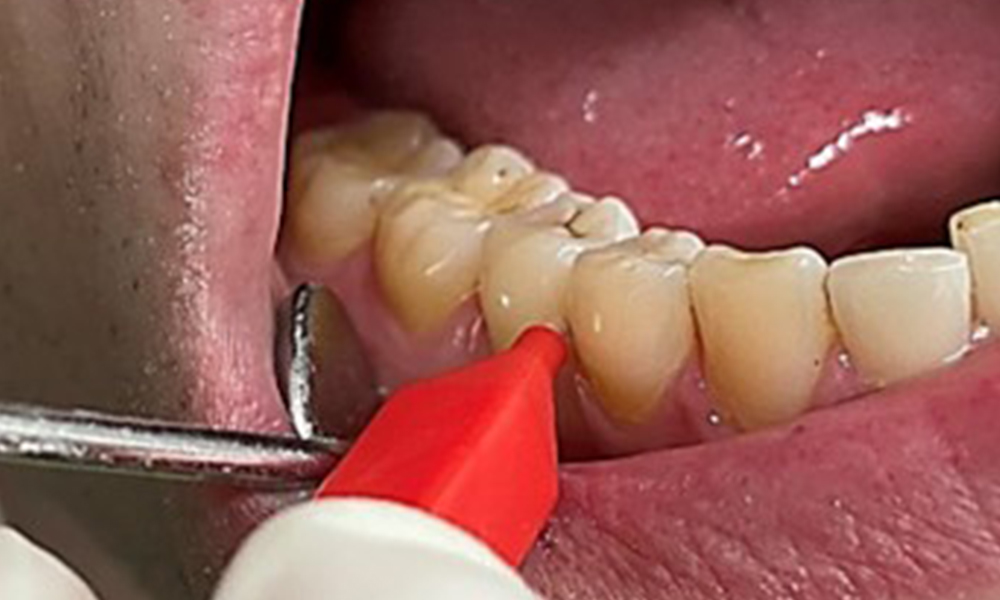

Ziel ist es durch supra- und subgingivale Biofilmentfernung das Erkrankungsrisiko zu kontrollieren. Die Wahl der Instrumente erfolgt

bedarfsgerecht. Zunächst sind Zahnstein und ggf. Konkremente mit Ultraschall und / oder Handinstrumenten zu entfernen (Abb. 10).

Die Raucher- und Teeverfärbungen lassen sich mittels Pulverstrahl gut entfernen (Abb. 11).

Bei Verwendung des höher abrasiven Pulvers ist dringend darauf zu achten von zervikal nach koronal zu arbeiten und die Auslassdüse niemals Richtung Gingiva zeigen zu lassen, um eine mögliche Emphysembildung zu vermeiden. Eine gegenüberliegende gute Absaugung ist unabdingbar zur Reduktion des Aerosols (Abb. 12).